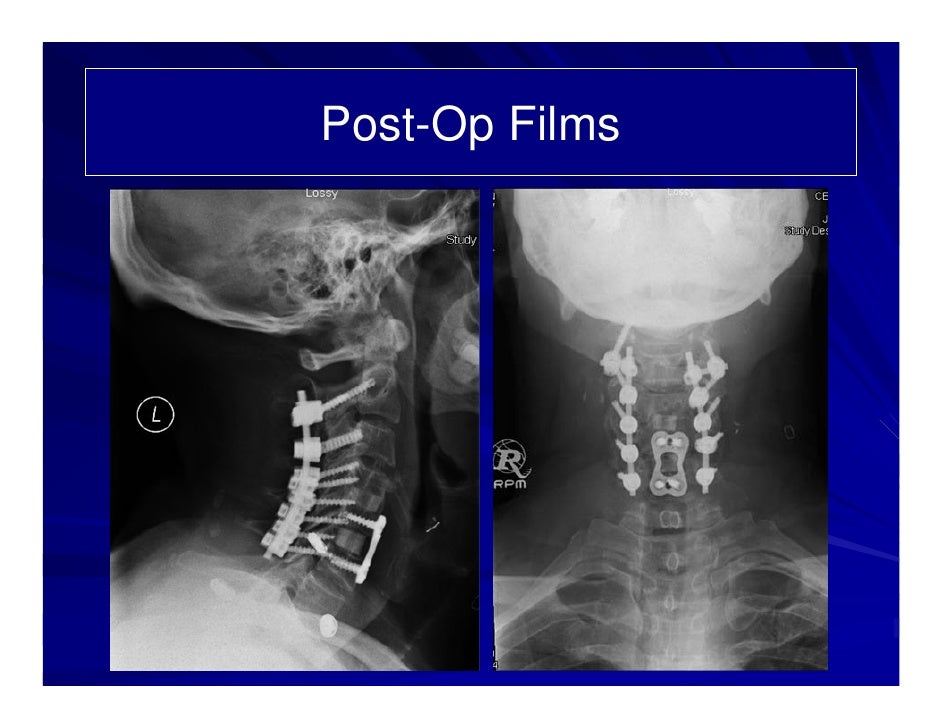

Case Review #5: 62 Year Old Male With Degenerative Disc Disease C2-C6

degenerative disease